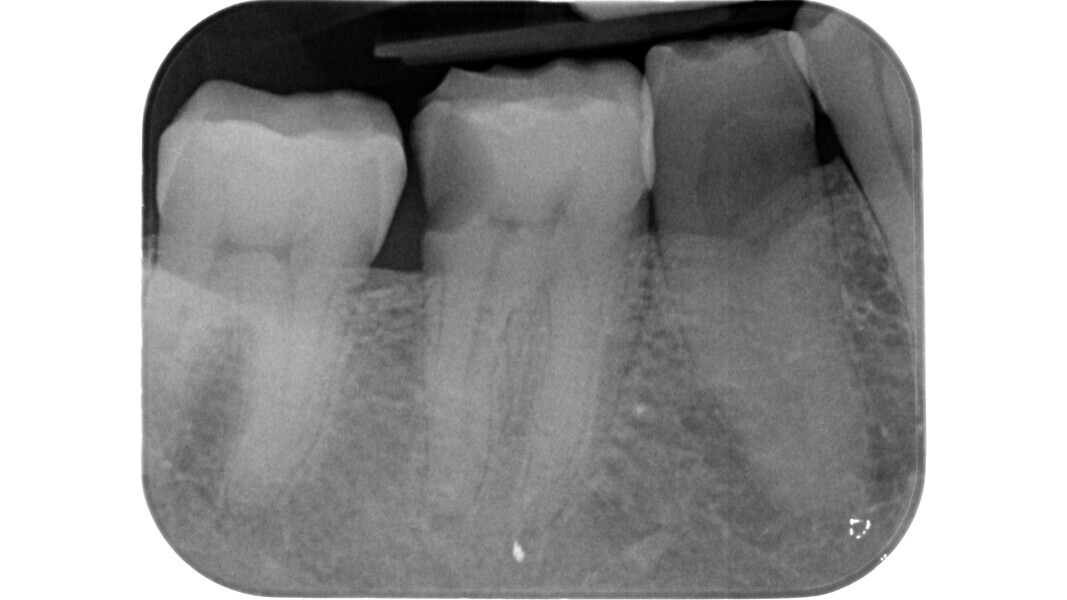

Fig. 1: Pre-op radiograph of a maxillary molar undergoing emergency treatment at another practice.

An inadequate access cavity in terms of position, depth and extension can lead to complications in the subsequent phases, making it impossible to locate the canal orifices, overstressing the mechanical nickel–titanium (NiTi) files or weakening the residual dental structure (Figs. 1–5). While, in the past, there was a tendency to emphasise the importance of a large access cavity that would allow the insertion of manual and mechanical instruments following the main axis of the canal, in recent years, the proposal of minimal access cavities defined in various ways (“ultra-conservative cavity”, “ninja cavity”, “truss access cavity”)4 has become predominant.